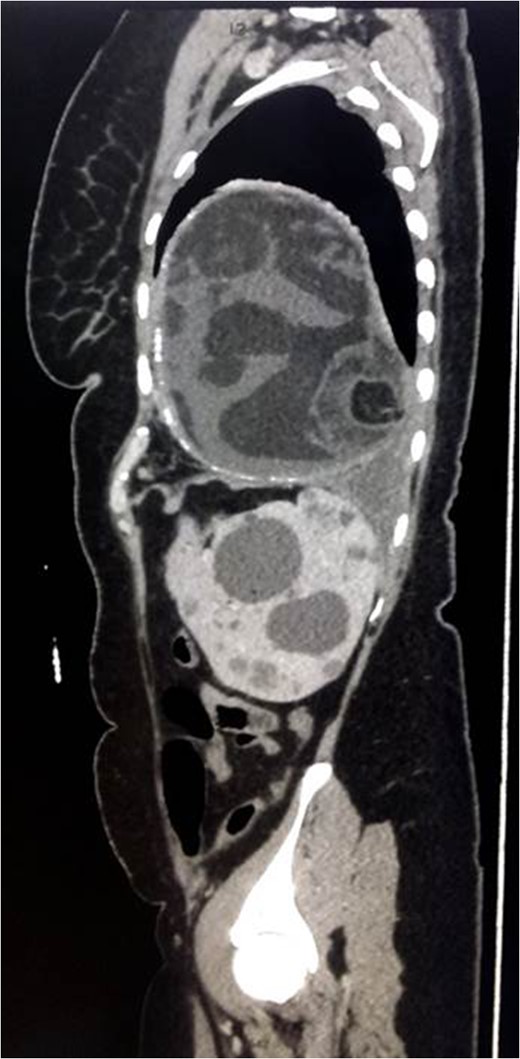

Chest x-ray showed well-defined huge opacity of most left hemithorax with a shift of mediastinum to the right (Fig. 1). CT chest/abdomen/pelvis with IV contrast revealed 20 × 15 × 18 cm3 well-defined mixed cystic lesion within the left lung containing multiple parts of the heterogeneous density with soft tissue elements and fat content. It also showed spots of wall calcification, where the lesion probably originated from the mediastinum, involving most of the left hemithorax. The mass compressed the mediastinal structures, great vessels, and airways (Fig. 2). It is surrounded by a consolidation collapsed with a marked shift of mediastinum to the right side (Figs 2 and 3). No mediastinal lymphadenopathy and the right lung was clear. The spleen was enlarged with multiple cysts that varied in size with no significant enhancement post IV contrast in arterial and portal phases (Figs 2 and 4). The liver was unremarkable. Hematological tests were within normal limits. Mantoux test and Sputum culture were negative.